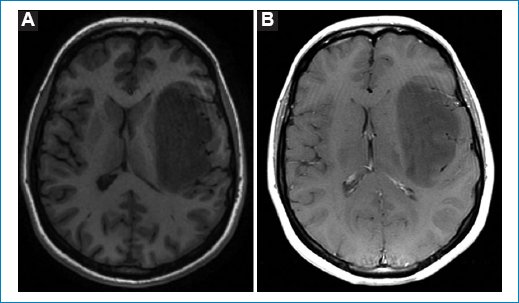

Las imágenes de resonancia magnética (RM) muestran una masa frontoinsular izquierda, hipointensa en la secuencia ponderada en T1 (Fig. 1), hiperintensa en T2 (Fig. 2) e hiperintensa en FLAIR (Fig. 3), pero con centro de menor intensidad. Este hallazgo, llamado “signo de la discrepancia”, es propio de las neoplasias gliales con IDH (isocitrate dehidrogenase) mutado y sin codeleción en 1p/19q1,2, y se observa en los astrocitomas. La codeleción 1p/19q es propia de los oligodendrogliomas3,4. La volumetría indica un volumen de 84 cm3 (Fig. 4).

Figura 1. Secuencia ponderada en T1. (A) Masa hipointensa en la región frontoinsular izquierda. (B) No se visualiza realce focal después de administrar contraste paramagnético.